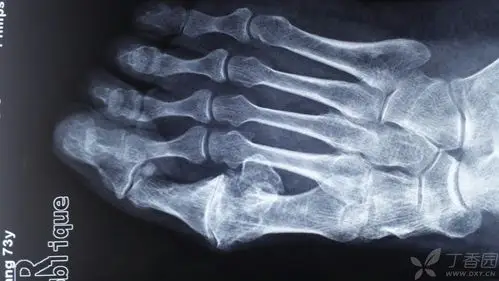

73岁男性,右足第一跖趾关节疼痛10年 - 骨科 -丁香园论坛